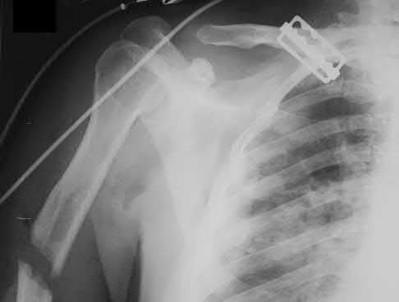

1024) An 18-year-old football player crossing the field to make a catch is hit on the shoulder and upper chest by the tackler and falls to the

ground with immediate pain throughout the shoulder region. The emergency department physician obtains the radiographs, CT scan, and 3-dimensional reconstructions seen in Figures 118a through 118e. What is the next step in management?

1. Obtain an MRI scan of the shoulder.

2. Place the arm in a sling for comfort and treat the injury nonsurgically.

3. Perform closed reduction in the emergency department.

4. Perform closed reduction in the operating room.

5. Perform open reduction using Kirschner wires to hold the joint reduced.

Corrent answer: 4

The player has sustained a posterior sternoclavicular dislocation. The CT scans show the medial end of the clavicle in close proximity to the aorta. An MRI scan will add no diagnostic information and might delay treatment. Nonsurgical management of an anterior sternoclavicular dislocation is often appropriate, but given the proximity of the clavicle to the aorta and airway, reduction of the dislocation is recommended to prevent vascular injury. While reduction is indicated, performing the reduction in the emergency department is not recommended because of the vascular injury or the need to perform an open reduction. Performing the procedure in the operating room with a thoracic surgeon available is recommended. Usually a closed reduction is stable, but if open reduction is necessary, Kirschner wires should be avoided to avoid the chance of migration of the implants.